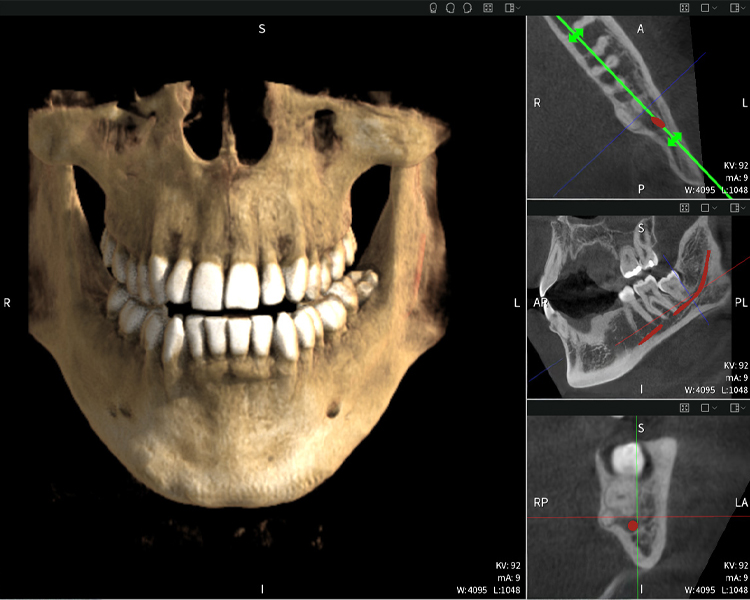

Below you will find a case from Dr. med. dent. Oliver A. Centrella, in which the CBCT images obtained with Seethrough Max provided crucial information on the complex anatomy and the critical relationship between the wisdom teeth and the inferior alveolar nerve. In this case, there is a indication for the surgical removal of the wisdom teeth.

Figure a: Imaging results of Seethrough Max, in front of a black background.

• Top left: Axial cross-section of the left mandible (region 38) showing the inferior alveolar nerve (red) in proximity to the roots of tooth 38.

• Top right: 3D reconstruction of the entire mandible for orientation. The red-marked inferior alveolar nerve illustrates its location within the jawbone.

• Bottom left: Sagittal view of the mandible (region 38), highlighting the close spatial relationship between the roots and the nerve canal.

• Bottom right: Coronal view of the mandible (region 38), which is crucial for assessing the spatial position of the roots relative to the nerve.

Figures b–d show various views of a 3D reconstruction of the mandible, providing a comprehensive overview of the mandibular anatomy, the position of the nerves in relation to the teeth, and allowing assessment of tooth symmetry and alignment.